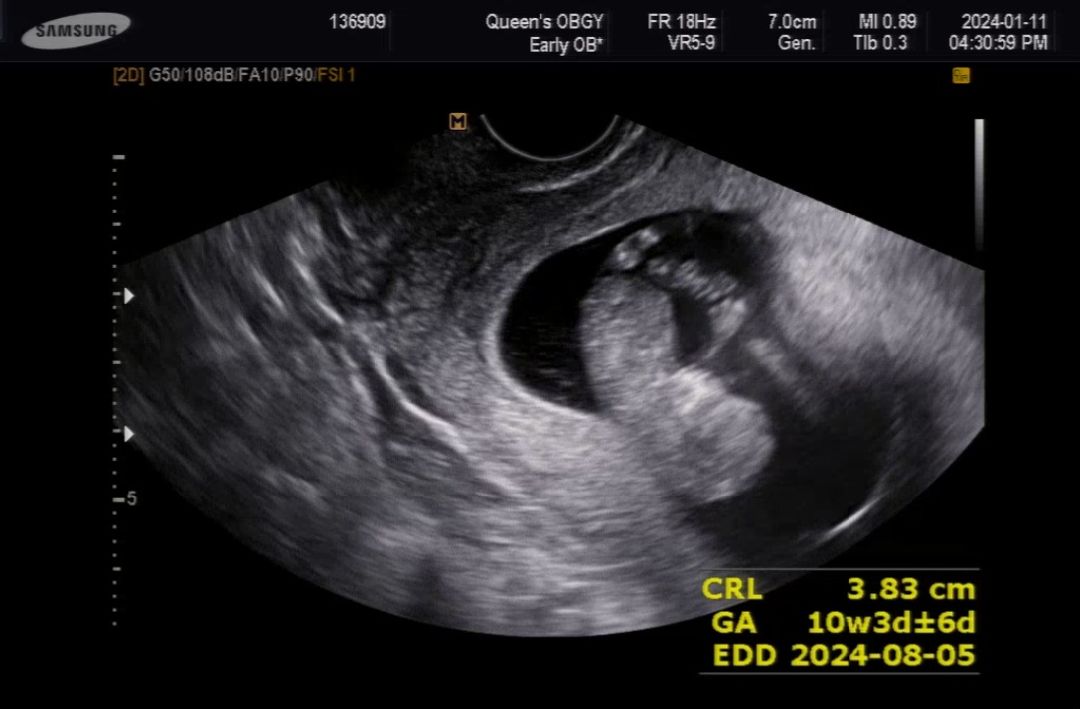

10주 3일 초음파

2주기다린 끝에 드디어 초음파보고왔네요 새벽에 피비침이 있어서 걱정많이했었는데 다행히 탯줄도 생겼고 크기도 알맞게 잘컸네요 손움직이면서 놀고있는 모습이 너무기여워서 2주 어떻게 참죠ㅜㅎㅎ

3cm인데 팔이랑 머리 혼자움직이는거 보니 신기하더라구요ㅎㅎㅎ